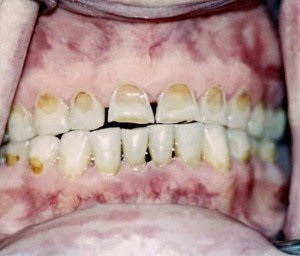

A fognyaki terület (az a hely, amely a legközelebb van a gumi) által alkotott kis mélyedést, és fokozatosan növekszik. Először is, ez nem észrevehető, hogy a beteg, mert a legtöbb szín nem nagyon különbözik a többi fogat. Figyelünk az eróziónak, amikor mélyül, így a fogak érzékennyé válik. Kellemetlen, éles fájdalom, amikor az oka a fogak megérinti a fogkefével, amikor eléri az édes cukorkát, savanyú narancs vagy egy hideg fagylalt. Kezdődik a kényelmetlenség és a beteg lebontja - mi történhet a fogat, mint, nézz a tükörbe, és nem, ez nem a fogszuvasodás. Beszéljünk arról, hogy mi okozza ezt a folyamatot, és hogy meg lehet csinálni.

- Mindig található a nyakát a fogak, a közvetlen közelében a fogíny, a száj (beszéd, a nyelv, a beteg a külső a fog). A fogzománc eróziójának - nyilván nem úgy néz ki, mint egy nyílás, és a mélyülő

- Ez egy színes hasonló a színe a fog, vagy enyhén sárgás. Bizonyos esetekben egy barnás színű (nézd meg őket az alábbiakban).

Vizuálisan, mint az erózió változhat barnás színű, és legyen minden foga csoportban.